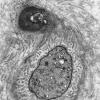

3 NORMAL MYELIN & SCHWANN CELLS

2 Node of Ranvier